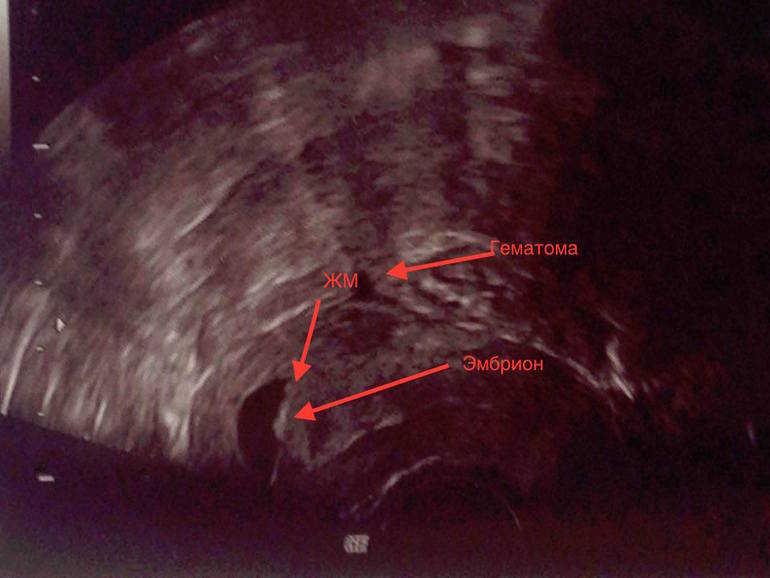

Фотограф из меня конечно никакой((( На самом снимке узи все четче в разы... Пузырик прям видно, хотя он и махонький. Попробовала подписать, как я это все вижу, эксперт блин))))

У нас тоже была гематома на раннем сроке, но это УЗИ в 5 и 4 недельки. Вообще я подумала,что гематома -это второй не прижившийся эмбрион. Уж очень они по форме и размерам близки

Слева эмбрион, справа гематома,с заостренным концом